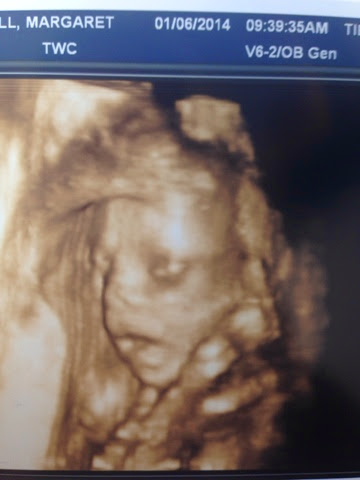

I'm including pictures that were taken throughout my pregnancy...